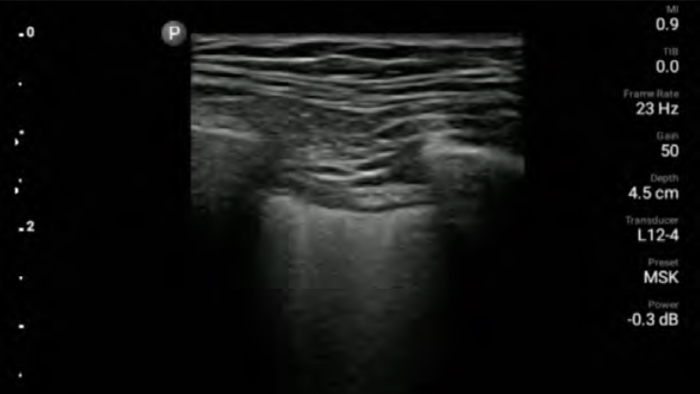

Reduce complications

in needle guided procedures

Lumify handheld ultrasound for anesthesiology helps you clearly visualize border definition with your needle placement, surrounding nerves, vessels and fascial planes.

Lumify helps you clearly visualize needle placement, surrounding nerves, vessels and fascial planes.

Lumify L12-4 broadband linear array transducer

• 12 to 4 MHz extended operating frequency range

• Aperture size: 34mm

• 2D, steerable color Doppler, M-mode, advancedXRES and multivariate harmonic imaging, SonoCT

• High resolution imaging for shallow applications: soft tissue, vascular, superficial, musculoskeletal and lung

• Center line marker

• USB-C transducer with replaceable cable